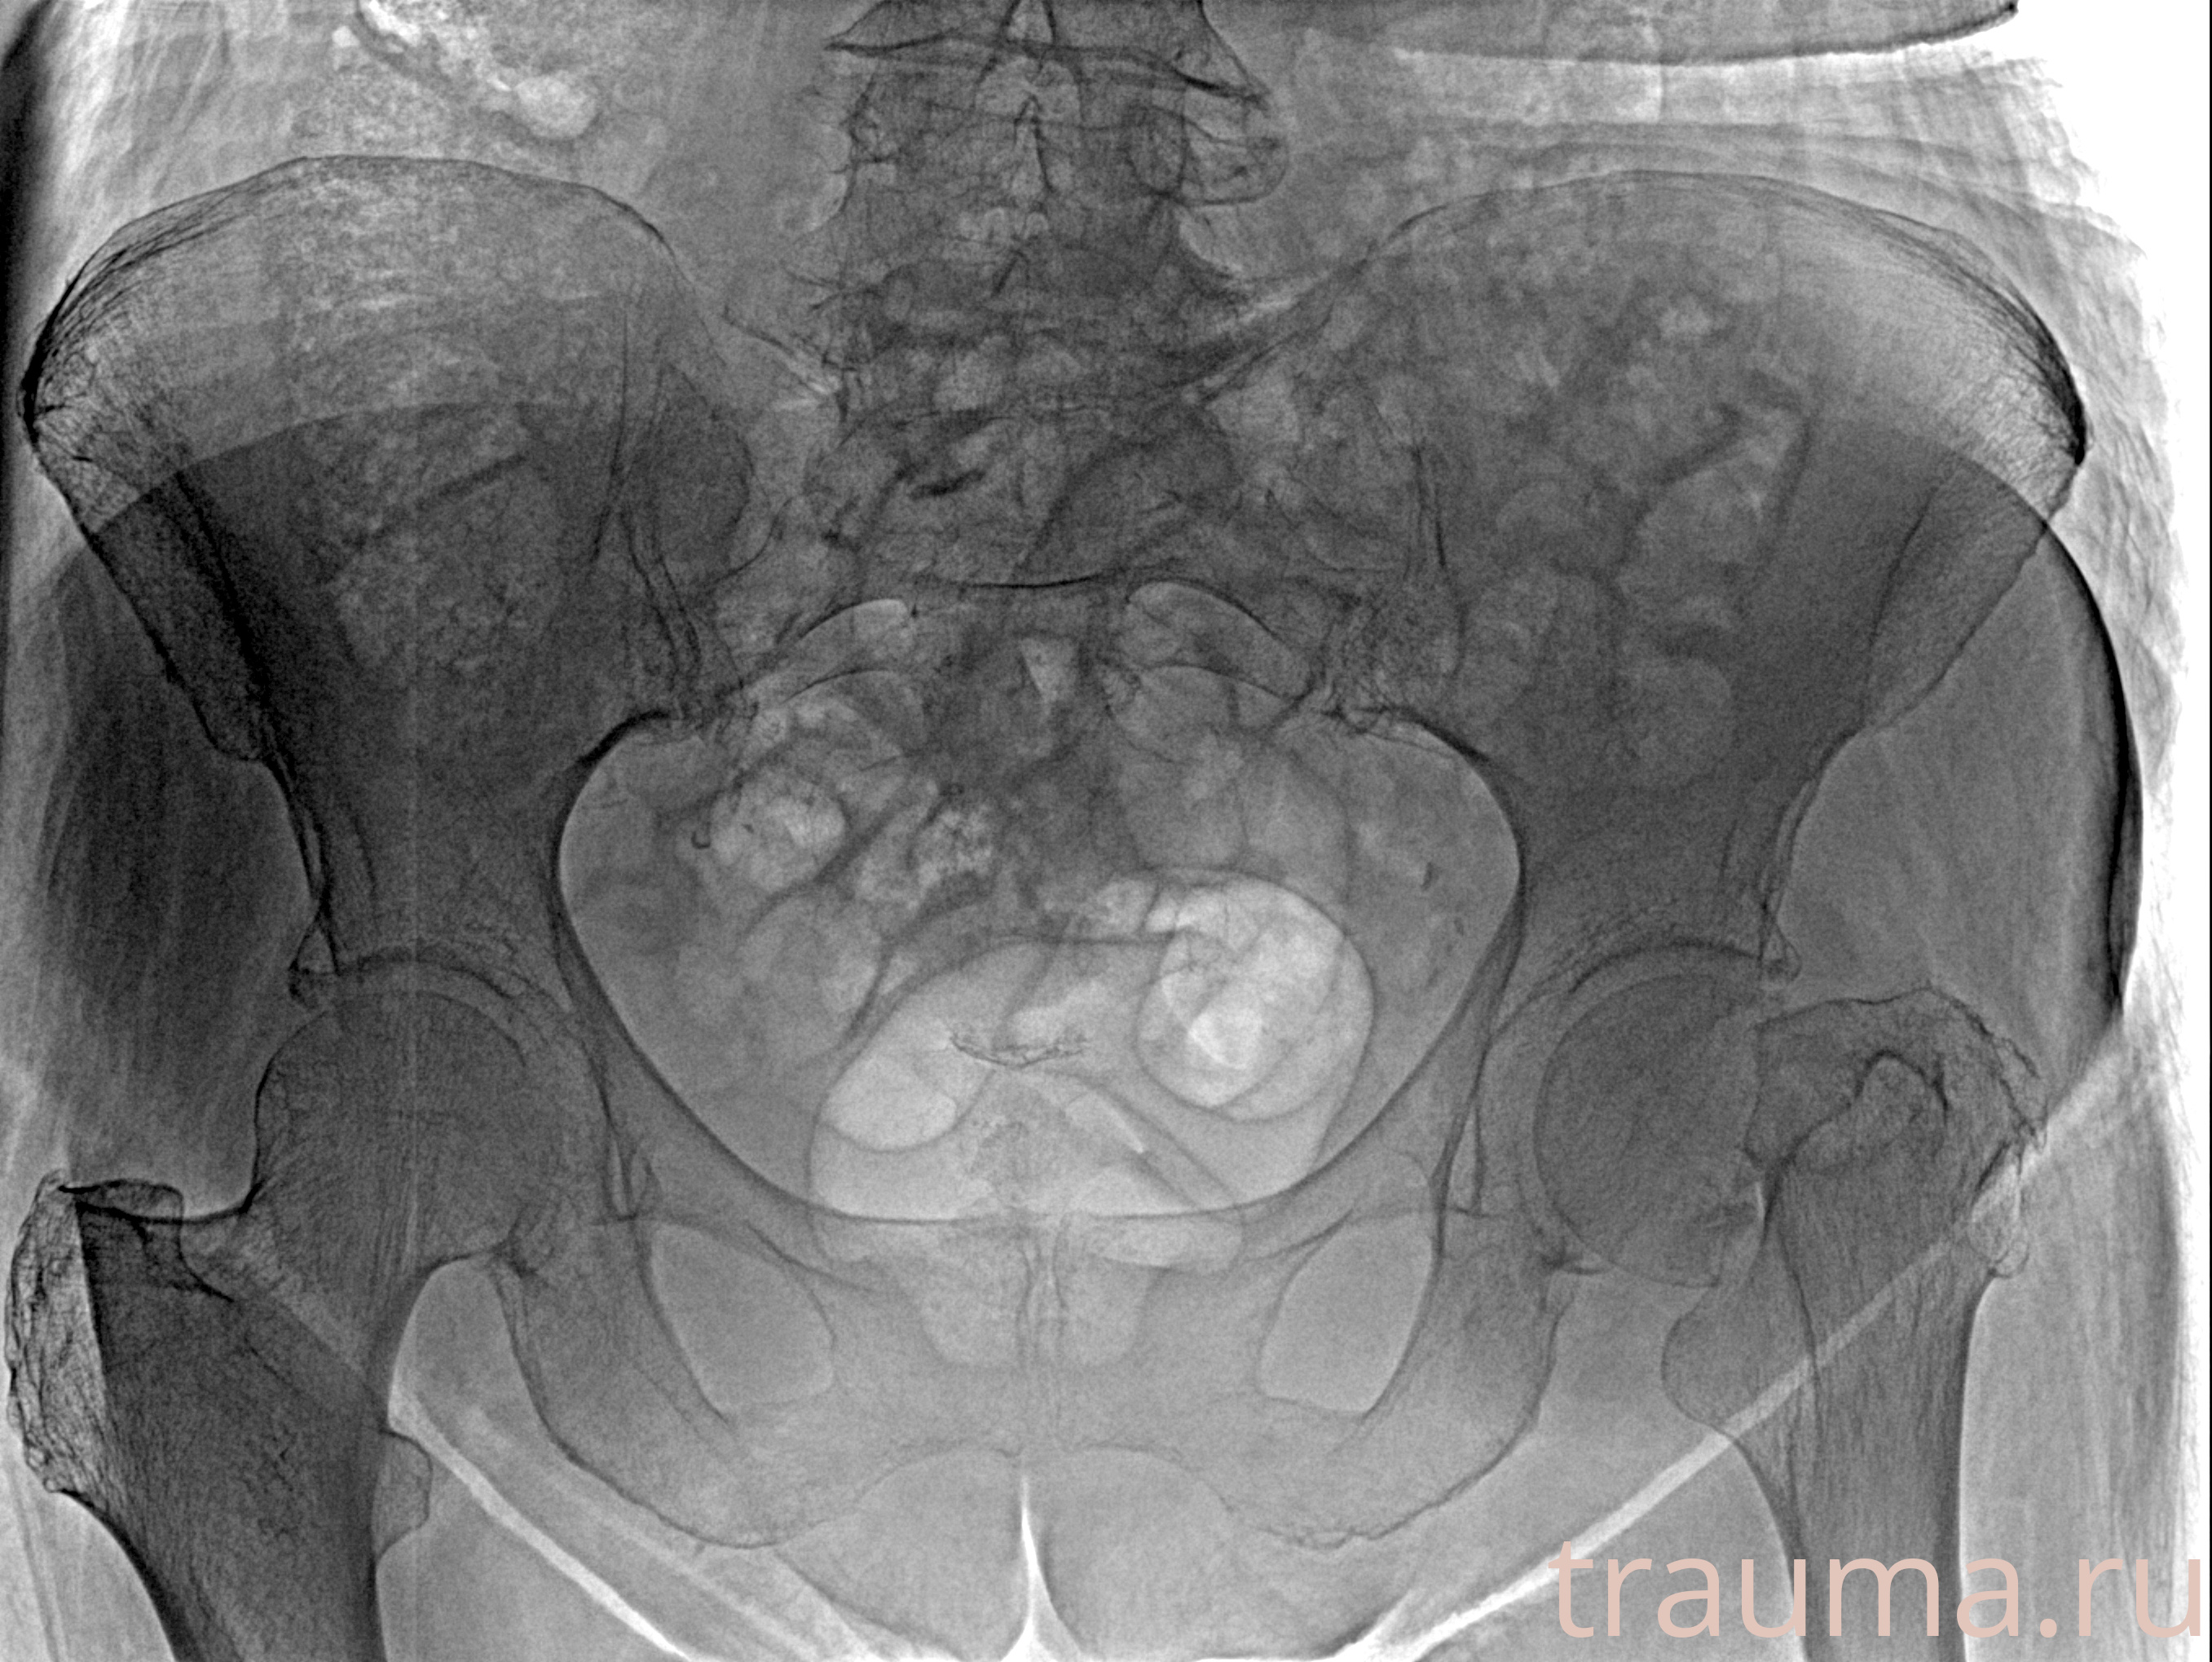

Рентген на дому: по вашему адресу приезжает врач-рентгенолог, травматолог-ортопед с мобильным рентгеновским аппаратом, проводит диагностику травмы или заболевания, делает необходимые рентгенограммы, дает рекомендации по дальнейшему лечению. Получить качественные снимки в домашних условиях возможно благодаря уникальной методике, разработанной МосРентген Центром для института  Склифосовского